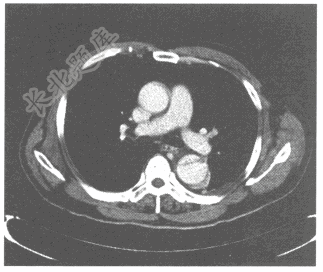

- 单项选择题男,55岁。突发胸痛就诊。胸部动脉CT造影如下图,可诊断是

A、主动脉血栓

B、主动脉夹层(DeBakeyⅡ型)

C、主动脉夹层(DeBakeyⅠ型)

D、主动脉瘤

E、主动脉夹层(DeBakeyⅢ型)